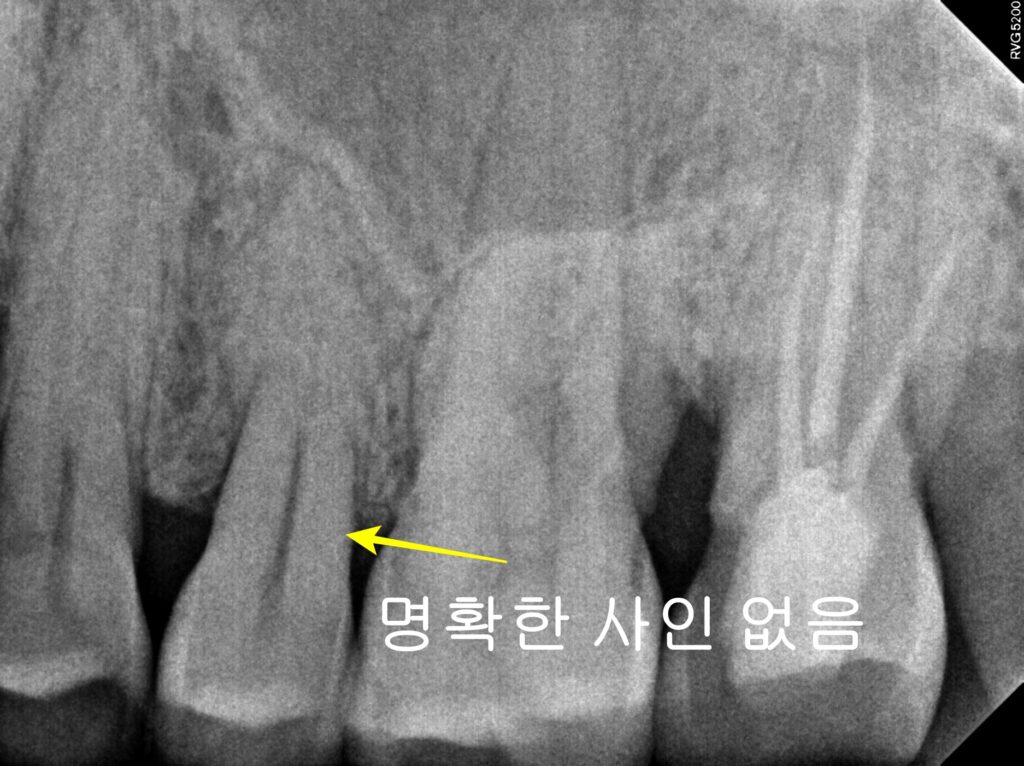

- X-ray 확인 불가: 미세한 금은 엑스레이상에 잘 나타나지 않습니다.

따라서 서울쏙쏙치과에서는 의심되는 치아의 특정 부위에 단단한 기구를 대고 씹어보게 하는 Bite Test(저작 검사) 를 통해 통증을 재현하여 정확히 진단합니다.